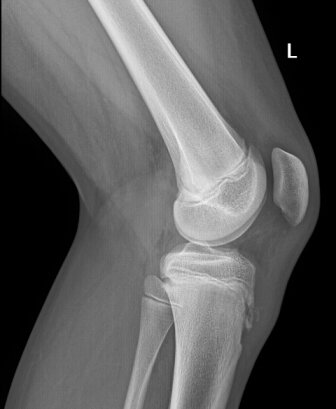

Вот так это выглядит на снимке